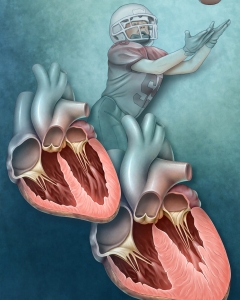

Internal Art Medical Illustration

Blending Art, Anatomy and Science for Creative Visuals

Patient & Professional Marketing

Welcome to my Patient and Professional Marketing page, where I harness the power of anatomical illustrations to educate and empower both patients and medical professionals. My unique approach combines artistry and education to convey complex surgical procedures and the utilization of medical devices in an easily understandable manner.